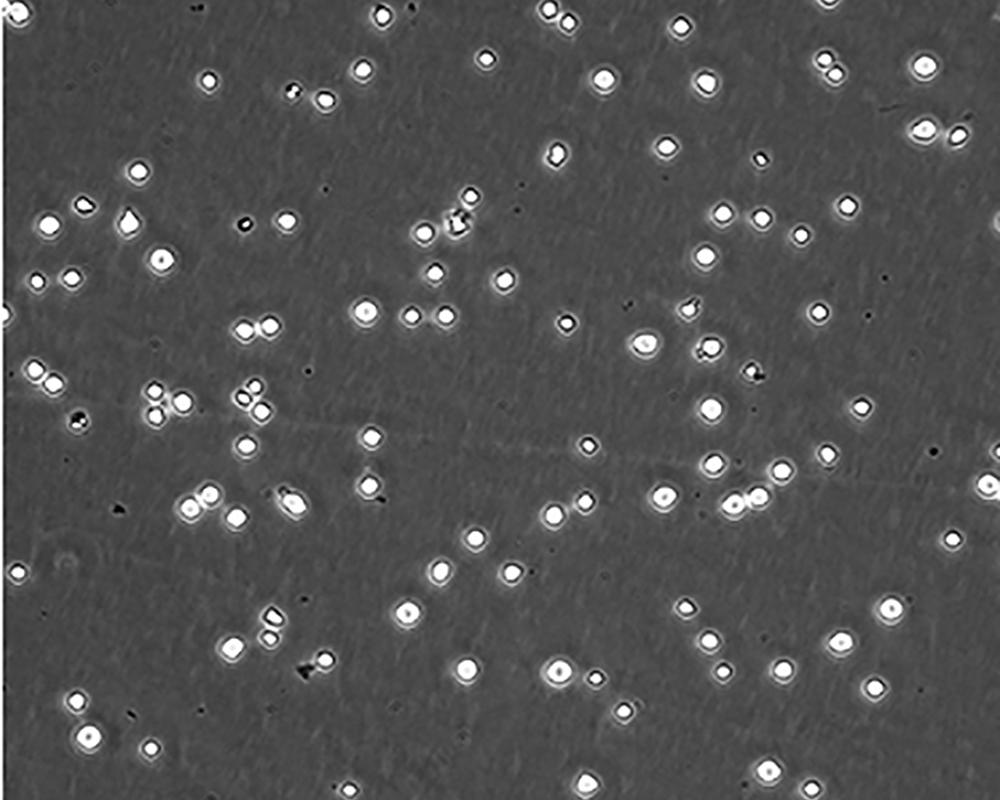

形態特征 lymphoblast

細胞描述 CEM/C1是人T細胞白血病細胞株CCRF-CEM(見ATCC CCL-119)具有喜樹堿抗性的衍生株。1991年細胞株選擇并亞克隆了對CPT的抗性。細胞表現出對CPT類似物水溶性的托泊替康和非水溶性的9-氨基-CPT及10,11-亞甲二氧基-CPT具有交叉抗性。CEM/C1細胞對CPT的敏感性較母系CEM細胞低31倍。CEM/C1細胞表現非典型的多藥抗性和轉換拓補異構酶I催化活性。對CPT的抗性維持6個月以上。